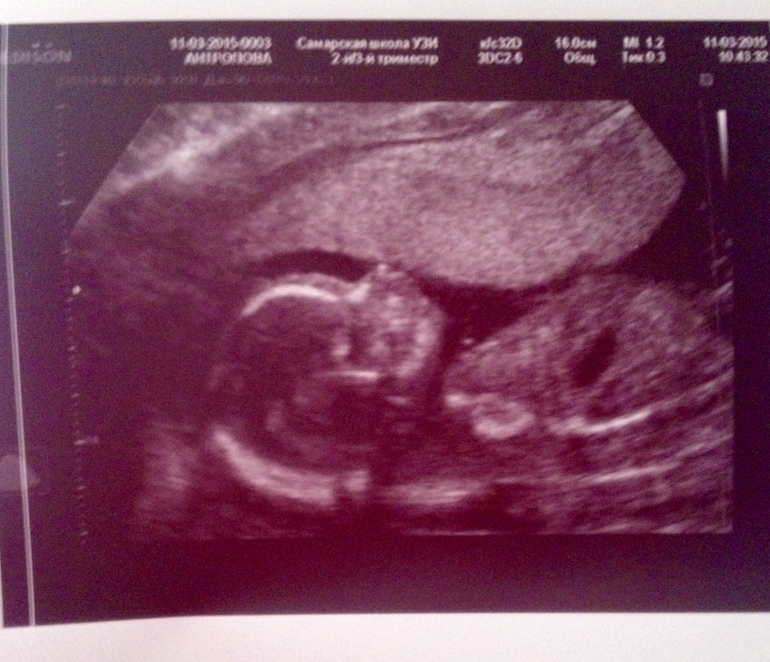

Врач в первые же секунды выдала "НУ ЭТО 100% МАЛЬЧИК" а сынок в это время на весь экран показывал нам свое мужское достоинство!!!😻😻😻😻😻😻😻😻😻😻😻😻😻😻

Эмоции переполняют!!! Дали нам две фоточки и диск в 2в и 4д формате))) врач чудесная, все рассказала показала, а малыш в это время весь крутился-вертелся и личиком в плаценту прятался. Все у нас , со слов врача, соответствует сроку, все хорошо и чудесно. Пуповина от шеи далеко, лежит сынок поперёк живота, ручками ножками машет шевелит!! Ой у меня все узи сердце в пятки уходило от счастья!!! Муж тоже распылился в улыбке когда сказали что мальчик))) потом когда в 4д лицо показали муж вообще обрадовался, так как малыш уже явно имеет что-то схожее с папочкой)))